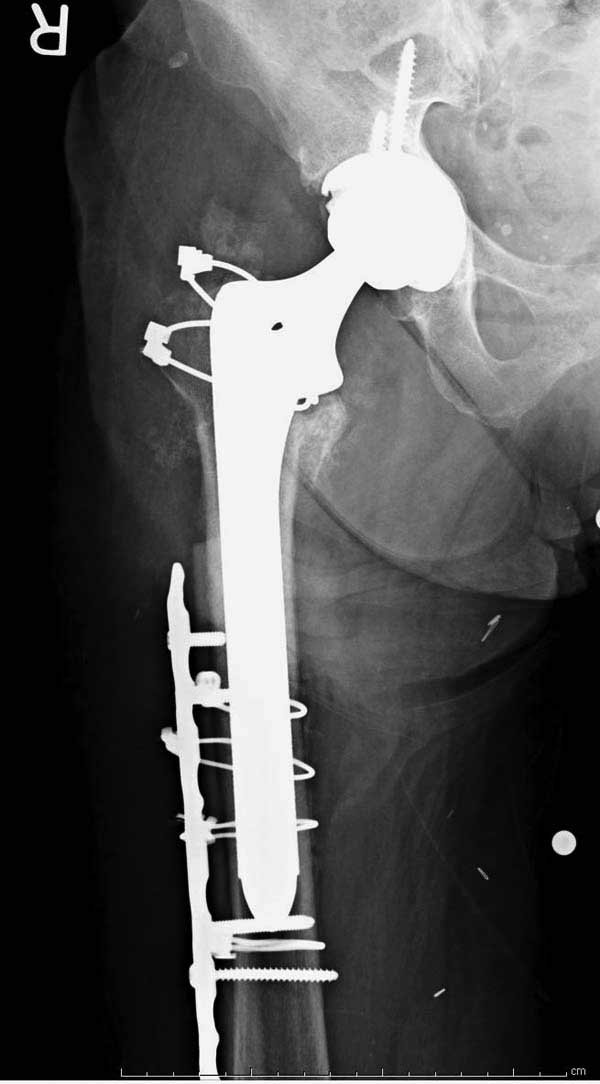

Сеньоры-пэры ревизировали гвоздем, шуруп поставили по той же дорожке, только поглубже. Да еще и bone graft не пожалели. "Результат" уже был через 2 дня.

Если сохранять головку - думаю надо было в валгусе фиксировать перелом гвоздем, или DCS, т.к. все-равно разрезали, чтоб достать DHS.

No comment.

End of story.

Неужели фиксация протеза бесцементная? Да и чашка не запрессована как надо.Грустно(

Эт -ж биполяр:)) Ножка цементная. Страйкеровский Exeter.1

Первые снимки показывают технические погрешности установки DHS. Не была достигнута репозиция, конечность в флексии и шейка в ротации. Сегодня все меньше обращают внимание на параметры для оценки репозиции (S контуры Lowell в обеих проекциях и Garden Alignment Index, в норме 155 и 180 градусов), хотя такие простые тесты помогли бы дорепонировать смещение. Винт находится сзади в головке, что при нагрузке поменяет вектор и вместо компрессии в линии перелома срежет головку-Cut Out!

Третья операция-продолжения усилии “синьорами пэрами” по разрушению нормальной анатомии. Крест на головку! По видимому возраст позволяет биполярную конструкции, и при дефекте calcar пошли на обычный цементный. Ягодичные мышцы потеряли связь с вертелом, т.е. отсутствует верхний удержатель, и результат “a Big Screw Up!” Снимки вызывают головокружение!

Если хирурги не устали от своих “творчеств”, тогда можно ре-оперировать с calcar replacement stem, и собрать остаток ягодичных мышц. Глубина и отстутствие артроза позволяет применить любой, биполярный или тотальный, хотя принять решение можно после ревизии ацетабулума.